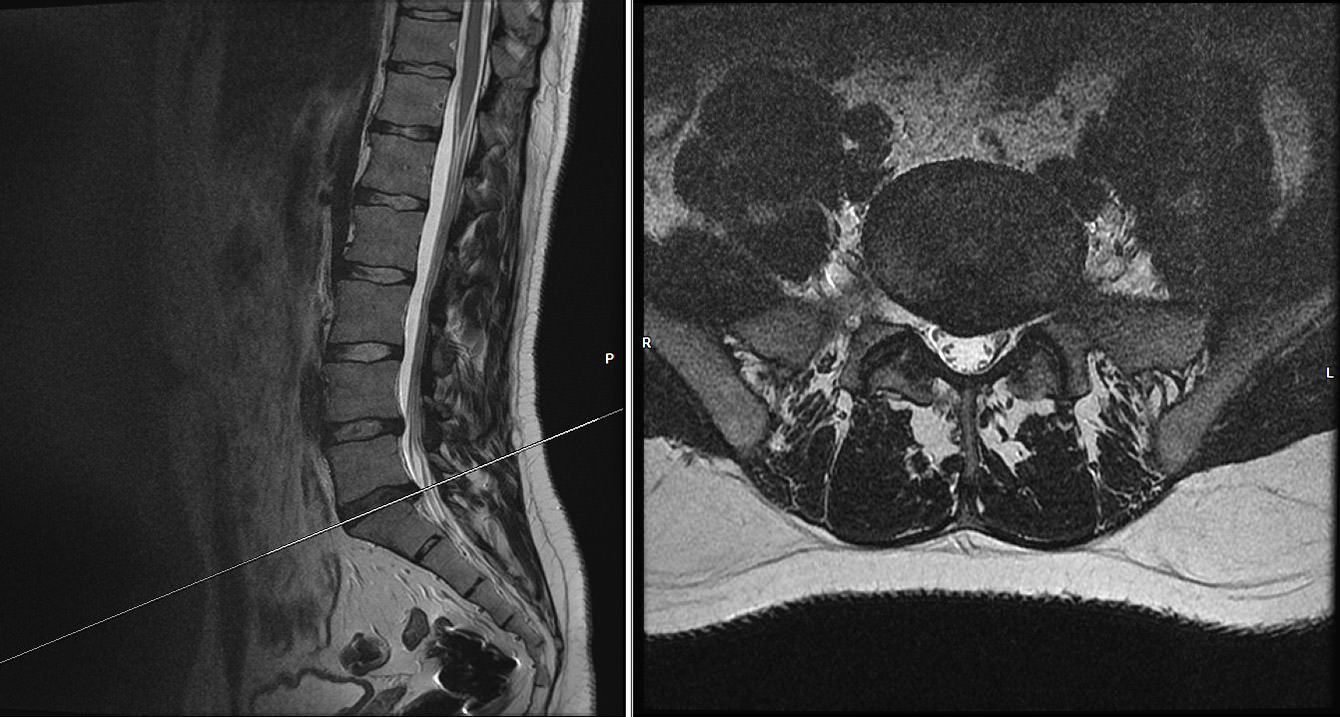

Die Kernspintomographie (Magnetresonanztomographie) ist ein modernes radiologisches Verfahren bei dem Bilder des menschlichen Körpers – ohne Röntgenstrahlen – mit Magnetfeldern und Radiowellen erzeugt werden. Die detaillierte Darstellung der anatomischen Strukturen ermöglicht es dem Arzt, kleinste Veränderungen zu identifizieren und präzise Diagnosen zu stellen.

Das offene MRT eignet sich zur Darstellung aller Wirbelsäulenabschnitte (HWS, BWS, LWS) incl. Becken, aller großen stammnahen Gelenke wie Schulter und Hüftgelenk sowie der Ellenbogen- und Handgelenke incl. Hand und der Gelenke der unteren Extremität wie Knie-/Sprunggelenke incl. Achillessehne sowie des gesamten Fußes.